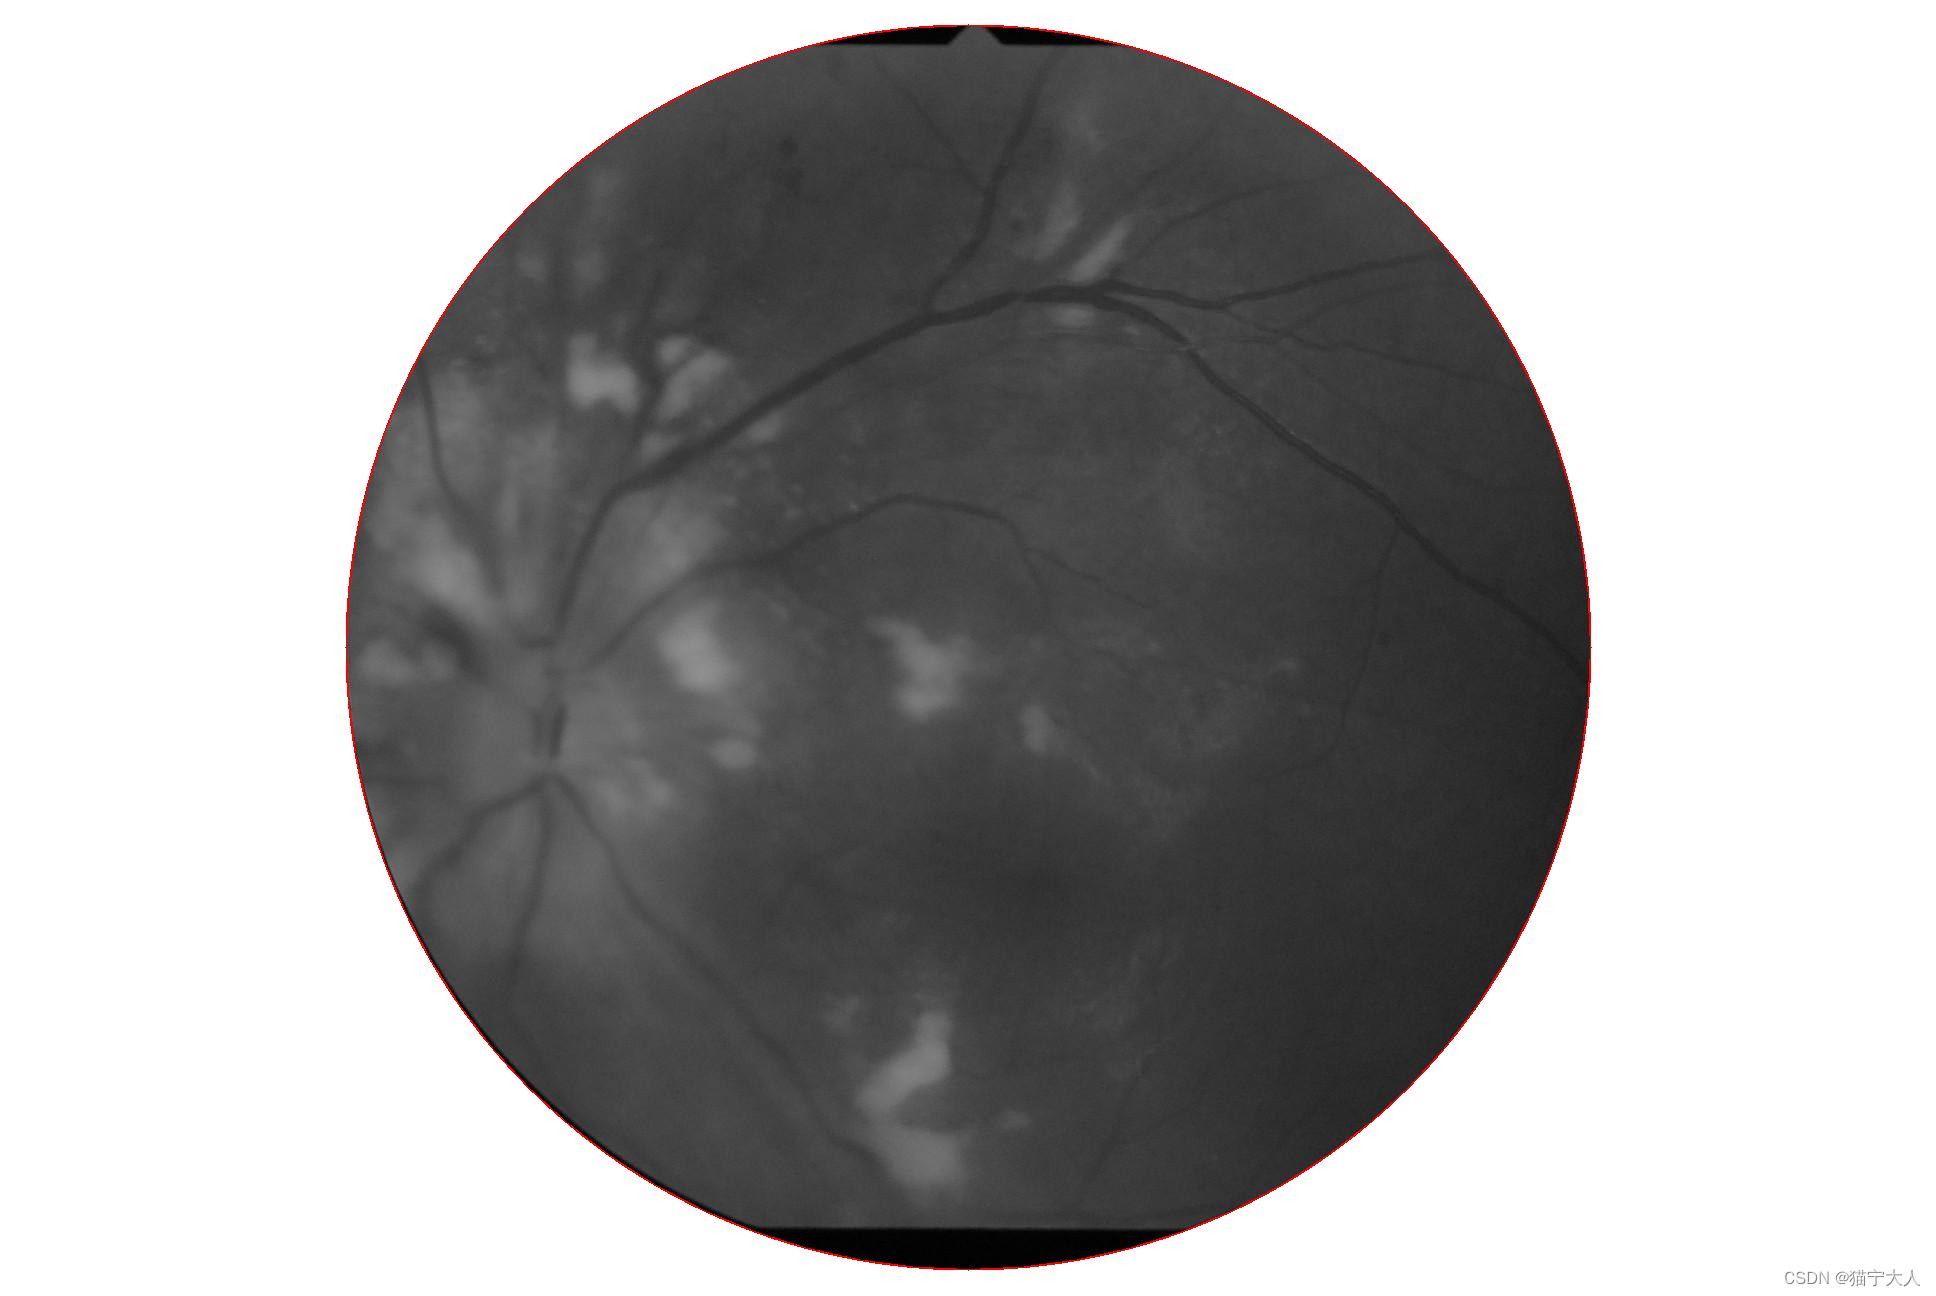

取圆后图像